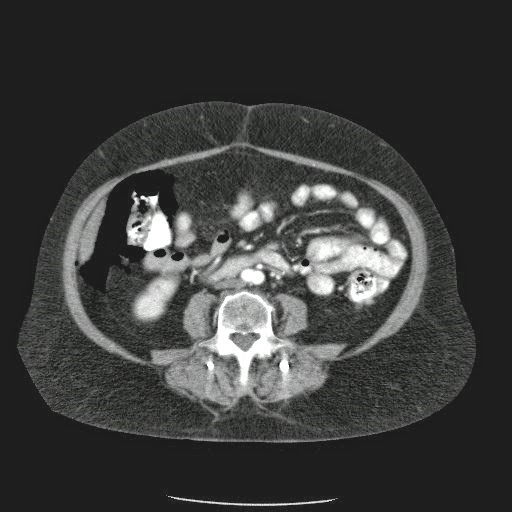

Caso Interesante #4

Adulto masculino, 1 semana de fiebre y malestar general.

¿Dónde esta ubicado el hallazgo?